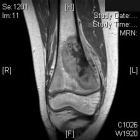

J.S. - 12 year old boy c/o right knee pain and swelling for ten days. Painful at rest, worse at night and with activity. Able to ambulate with pain. Initially the pain was accompanied by fever, chills, malaise, nausea and vomiting; all of which have resolved.